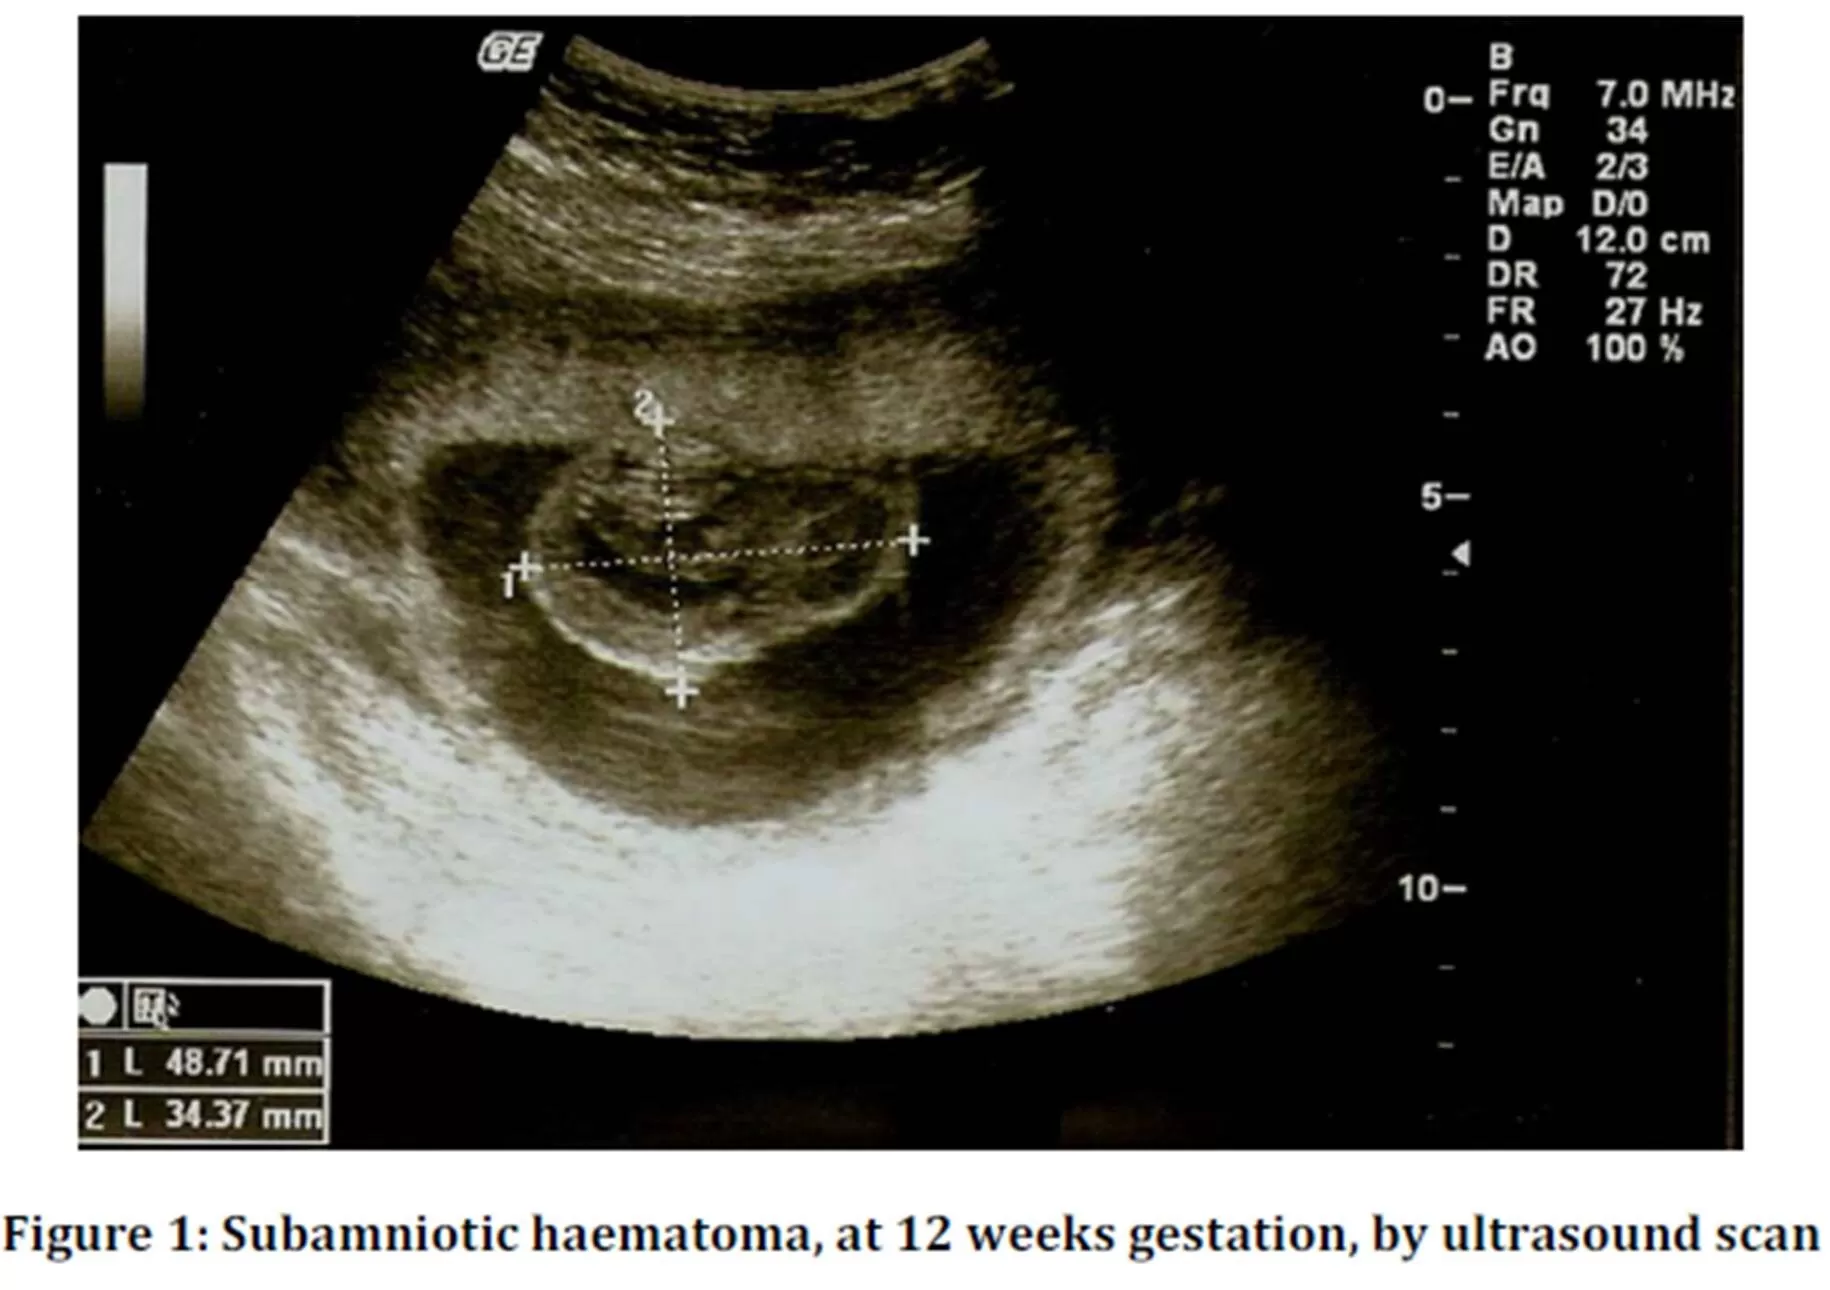

In the 1st trimester ultrasound scan, at 12 weeks gestation, it was observed a hypoechogenic image, indissociable from the placenta, with 49 mm of diameter — see figure 1.

Colour Doppler showed no blood flow. The umbilical cord showed no abnormalities, with 3 vessels and central insertion in placenta.